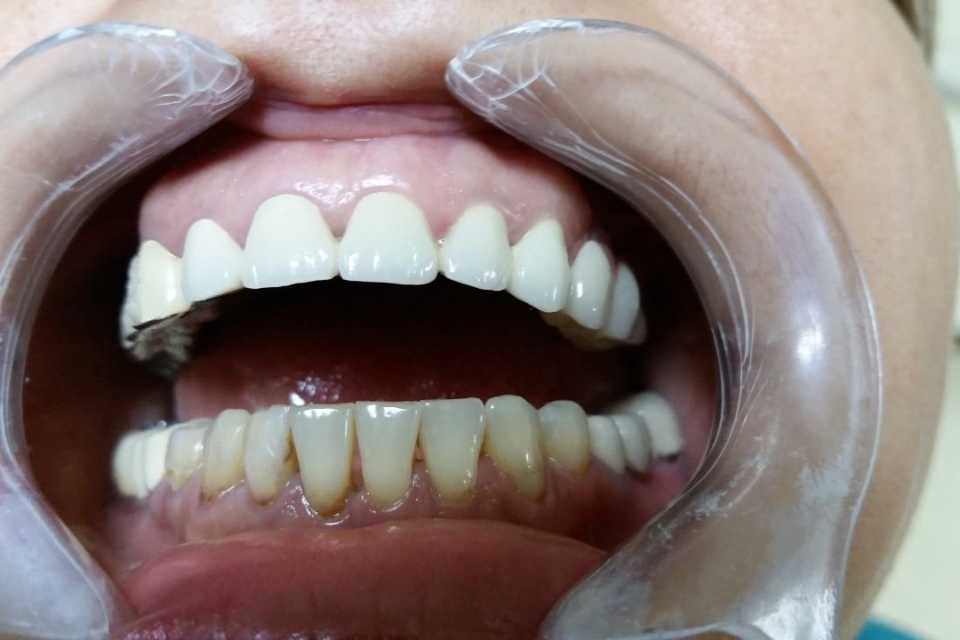

Protezare dinți frontali superiori cu lucrare ceramică

Pacienta s-a prezentat din motive estetice, cu probleme în zona frontală superioară. De comun acord am stabilit protezarea dinților frontali superiori printr-o lucrare ceramica (D'sign). După ablația vechilor coroane, tratamentele endodontice, refacerea bonturilor cu pivoți din fibră de sticlă, înregistrare cu arcul facial (la tehnician) și șlefuirea dinților, am obținut rezultatul mult dorit din punct de vedere estetic și funcțional.

Pentru executarea ireproșabilă a coroanele și punților dentare recomand șlefuirea cu prag.